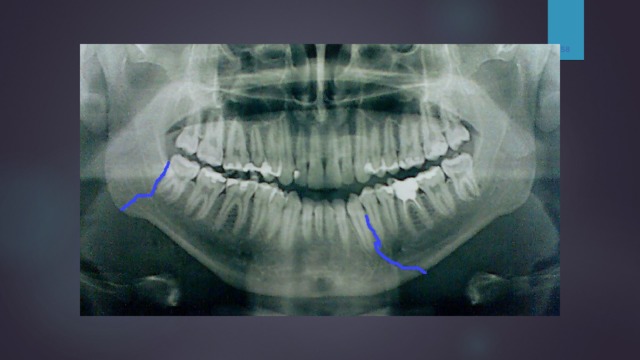

Рентгеновские снимки посттравматического остеомиелита челюсти: Медицинские случаи

Раздел: Образы вокруг